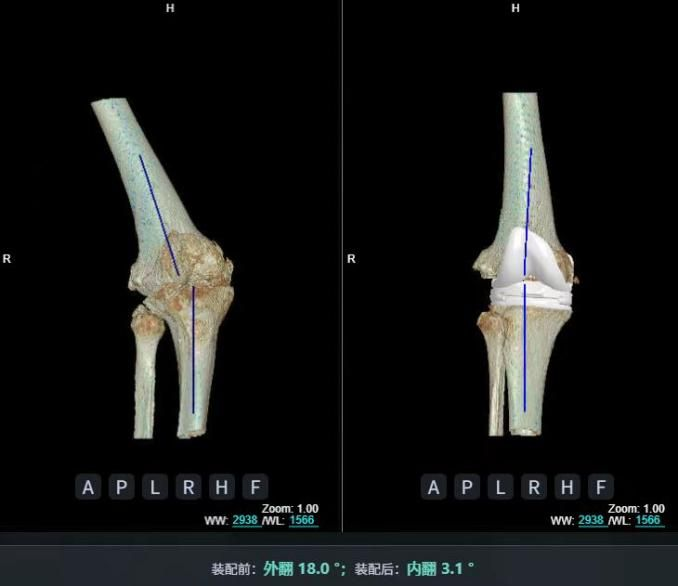

4.2 APTT-HTO脛骨高位截骨術

2025年7月,貴州醫科大學附屬醫院骨科團隊原創研發的腘肌前結節中脛骨高位截骨保膝術(Anterior Popliteus Transtibial Tuberosity-High Tibial Osteotomy, APTT-HTO)及其提出的脛骨結節分區與腘肌保護理論,登上了國際頂尖學術舞臺。該成果在全球最具影響力的專業會議之一——日本骨科協會第98屆年會上進行了兩次學術發言。[8]

貴州醫科大學附屬醫院骨科團隊

該手術具有經皮微創、保留原生膝關節結構、符合階梯治療原則等優勢,通過調整下肢力線可促進部分軟骨再生,術后關節功能接近正常(如下蹲、爬山),患者還能從事中重體力勞動。相比其他術式,其有效規避了髕骨低位、血管損傷、合頁骨折等潛在并發癥。

目前,APTT-HTO技術已成功應用于千余名患者,幫助保留自身膝關節。此類保膝手術適用于單間室膝關節炎患者(如 “羅圈腿”),核心是通過調整力線糾正畸形,減輕磨損間室壓力、發揮健康間室作用,延長膝關節壽命。若出現膝關節疼痛、保守治療無效且X線顯示關節間隙部分狹窄,建議及時就醫評估是否適合手術。